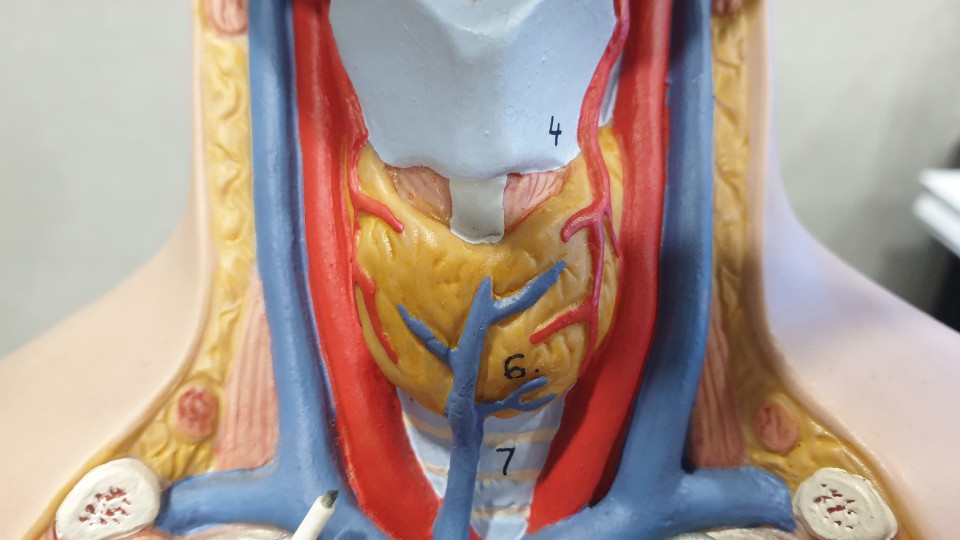

가운데서 노랗게 보이는 것이 갑상선입니다. 갑상연골 아래에 위치합니다.갑상선도 혈관을 통해 영양소를 공급을 받고 있는 것 같은 느낌이 듭니다.